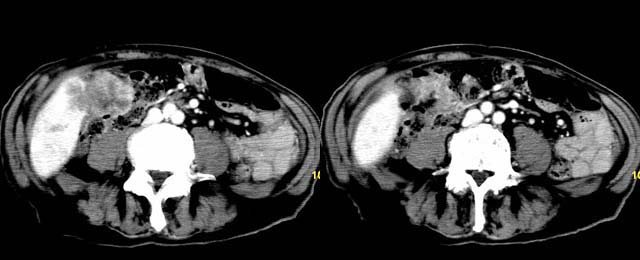

以下是引用余辉在2007-12-6 22:23:00的发言:[br]胆囊内多枚结石影,胆管全程扩张,右肝内病灶强化符合脓肿表现现(左肝病灶图像未传完),考虑急性梗阻性化脓性胆囊胆管炎合并肝多发脓肿(建议补传左肝病灶图像)